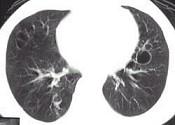

问题 女,23岁,咳嗽咳痰反复发作,根据CT图像,应考虑为 ( )

选项 A.支气管扩张并感染 B.多发肺气囊肿 C.多发性肺囊肿并感染 D.多发性肺脓肿 E.大叶性肺炎

答案 C